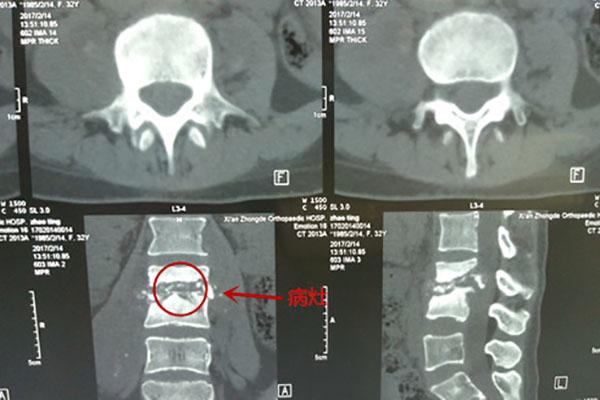

滨医医院用椎间孔镜清除脊柱结核病_健康频道

600x473 - 37KB - JPEG

脊柱结核起病隐秘 误诊结果严重 你一定要了解

600x400 - 47KB - JPEG